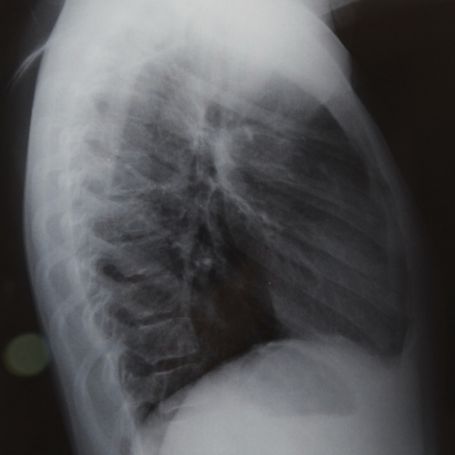

The X-Ray Shoulder AP/LAT (Anteroposterior and Lateral views) is a specialized diagnostic imaging test used to visualize the bones, joints, and surrounding structures of the shoulder. At Diagnopein, we use advanced digital X-ray technology to deliver clear, detailed images that help doctors diagnose various shoulder conditions accurately.

The AP (Anteroposterior) view shows the shoulder from the front, helping identify dislocations, degenerative diseases, and fractures. The Lateral view provides a side image, allowing doctors to examine overlapping bone structures and joint spacing.